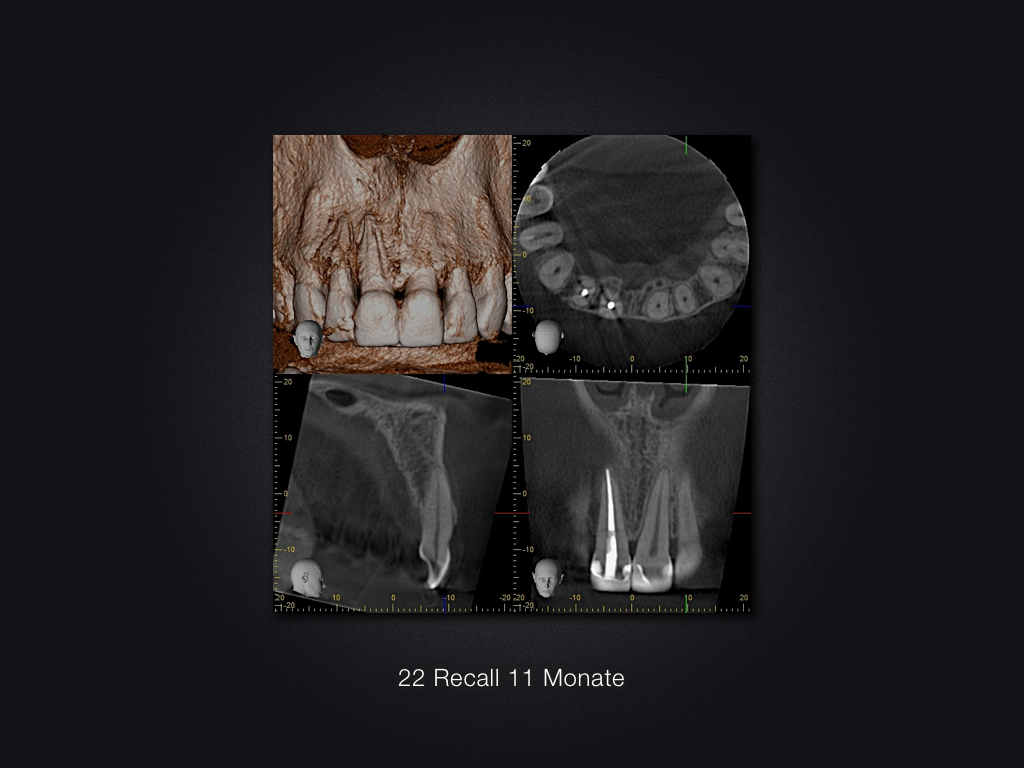

11 21 D.019

Recall nach Frontzahntrauma